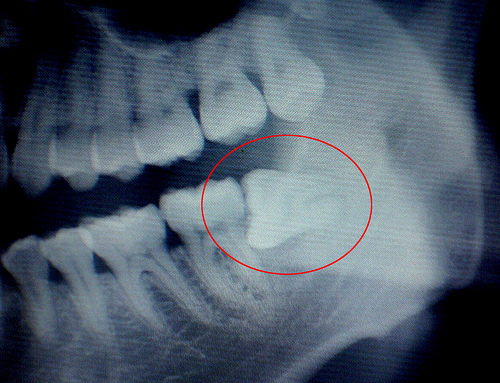

2、智齿横向生长,别的牙齿都一柱擎天向上长,偏偏智齿会长得横行霸道,一旦碰触到旁边的牙齿,自然会出现牙疼的情形。如果智齿长成这样,务必趁早拔掉;

3、智齿“蜗居”在牙肉里,有时候你根本就看不到智齿,但依旧会觉得牙疼难当,基本就是这种原因所致。